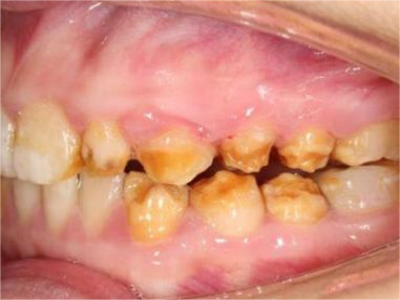

牙釉质发育不全牙齿上棕色的坑图

牙釉质发育不全程度严重时,牙齿上出现较深的条状、点状凹陷,内含深褐色物质,并且牙齿尖端的牙釉质缺失,牙齿变得相对脆弱。

牙釉质发育不全牙齿棕色有缺损图

牙釉质发育不全患者牙齿出现明显的缺损表现,并于表面形成深褐色的蜂窝状、竖条状的凹坑,甚至形成洞,患者上下牙失去咬合能力。

牙釉质发育不全牙齿表面棕色有坑图

牙釉质发育不全导致牙釉质表面呈棕褐色,有带状、窝沟状凹陷,以及黑点,牙釉质大面积缺损,牙齿表面变得粗糙,可出现进食时敏感等不适。

牙釉质发育不全牙面上棕色小坑图

重度牙釉质发育不全患者牙面出现带状或蜂窝状棕色小坑,累及多个牙齿,无明确的分布规律,严重影响牙齿美观,建议通过牙齿修复治疗恢复牙齿外观。

牙釉质发育不全牙齿中间有棕色条纹图

重度牙釉质发育不全患者牙齿表面呈棕褐色,牙釉质大面积缺损,其上有并列的条状凹陷,部分牙尖缺损,导致咬合关系被破坏,并出现疼痛等自觉症状。

牙釉质发育不全牙齿发黄缺损图

牙釉质发育不全发展到严重程度时,牙釉质表面呈棕黄色,表面有褐色凹陷,并且导致牙釉质大面积缺损,部分牙齿甚至有牙尖缺损。

牙釉质发育不全牙齿缺损有小坑图

重度牙釉质发育不全导致牙釉质表面呈棕褐色、棕黄色,其上有条状、窝状凹陷,并出现牙齿缺损,导致咬合关系破坏,也会出现对刺激敏感、疼痛等自觉症状。

牙釉质发育不全牙齿缺损图

牙釉质发育不全磨牙后,牙齿表面的牙冠快磨没了,出现牙齿缺损现象,露出牙髓,缺损面粗糙不平,同时存在牙龈肿胀、牙齿松动或移位等现象,肉眼可见缺损面颜色发黄或发黑。